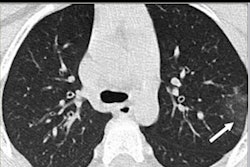

The U.S. Food and Drug Administration (FDA) is allowing medical artificial intelligence (AI) software developer CuraCloud's new deep learning-based algorithm to be used for the detection and prioritization of incidental pneumonia findings associated with COVID-19. The findings stem from noncontrast chest CT images.

The firm's CuraRad-ICH algorithm analyzes noncontrast head CT images for the detection and prioritization of intracranial hemorrhage patients, but CuraCloud is enhancing its software to process chest CT exams. The results can be used to enable the algorithm to notify the radiology worklist that the image includes findings suggestive of pneumonia associated with COVID-19.